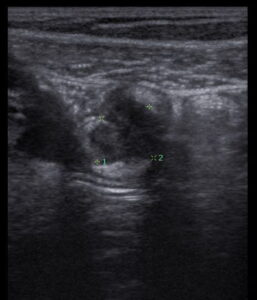

Ultrassom transvaginal com preparo intestinal mostrando a estratificação de uma alça intestinal normal.